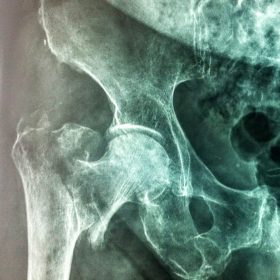

Υποκεφαλικό : Είναι ενδαρθρικό κάταγμα στον αυχένα του μηριαίου (το εσωτερικό του αρθρικού θυλάκου), το οποίο διακόπτει την αιμάτωση της κεφαλής του μηριαίου και οδηγεί σε μη πόρωση του κατάγματος (ΟΣΤΕΟΝΕΚΡΩΣΗ της Μηριαίας κεφαλής). Σε ασθενείς κάτω των 65 ετών αντιμετωπίζεται χειρουργικά με κοχλίωση στις πρώτες 12 ώρες. Τρείς βίδες σε σχήμα Τ με την βοήθεια τηλεόρασης διαδερμικά χωρίς διάνοιξη. Σε ασθενείς από 65-75 ετών γίνεται ολική αρθροπλαστική και σε ασθενείς άνω των 75 ετών αλλάζεται μόνο η κεφαλή χωρίς την αλλαγή της κοτύλης. Ο ασθενής περπατάει άμεσα μετεγχειρητικά στις 5 ώρες και εξέρχεται από το νοσοκομείο σε 1 -2 ημέρες. Στην κοχλίωση μπορεί να εξέλθει και την ίδια ημέρα.